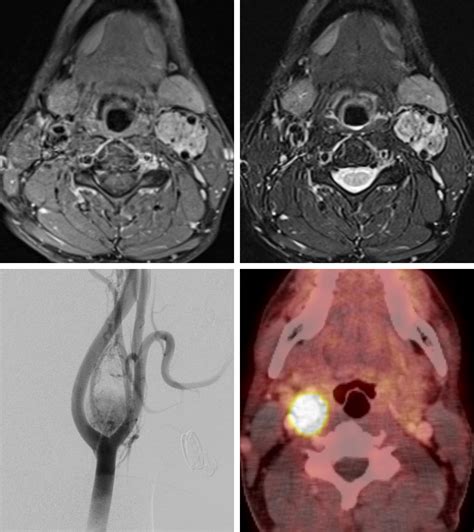

• Imaging studies: Various imaging techniques are used to visualize the tumor and determine its size, location, and extent. Common imaging studies include:

Magnetic Resonance Imaging (MRI) Offers high-resolution images of soft tissues and can help differentiate the tumor from surrounding structures.

Angiography Involves injecting a contrast dye into the blood vessels to visualize the tumor's vascular supply and plan for surgical intervention.